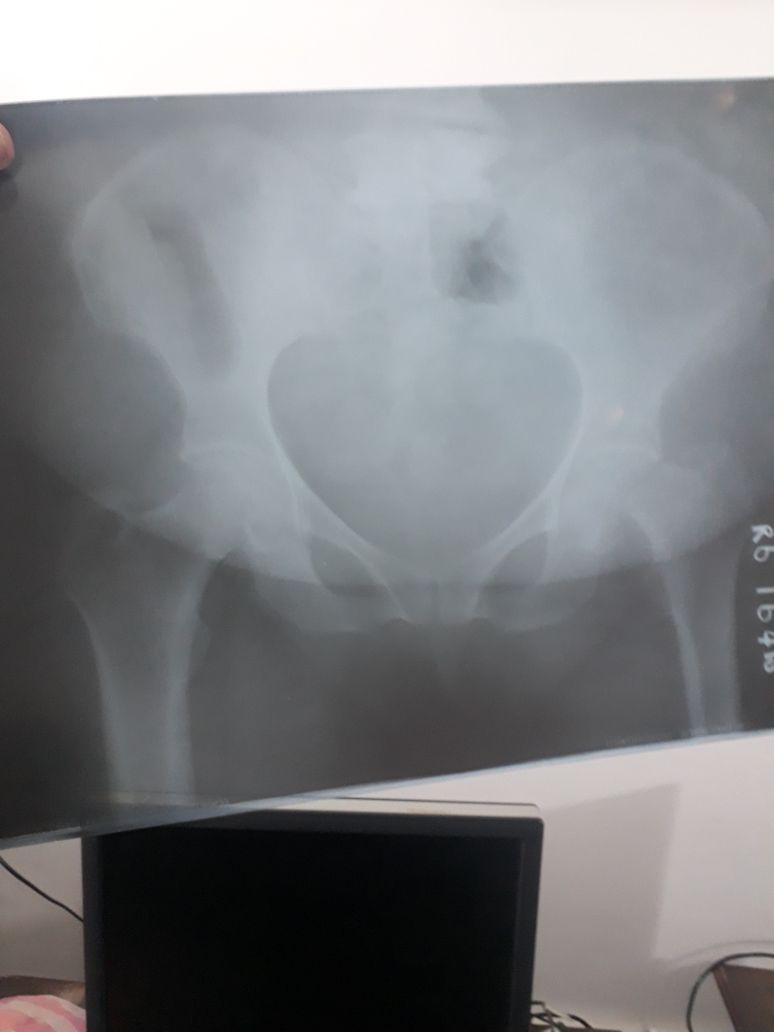

She had a fracture unable to stand and walk we got the first opinion from orthopedic surgeon and adviced for surgery. Looking forward for second opinion and advice .

Yes Pt require surgery.

Needs surgery thanks

when hip bone is fractured, surgery gives best result. she can start walking next day and good recovery.

you can leave it without operation but she will be in pain for long time and will not be able to walk for few weeks.

She does need immediate Surgery. And delay can cause complications and lower success rate.